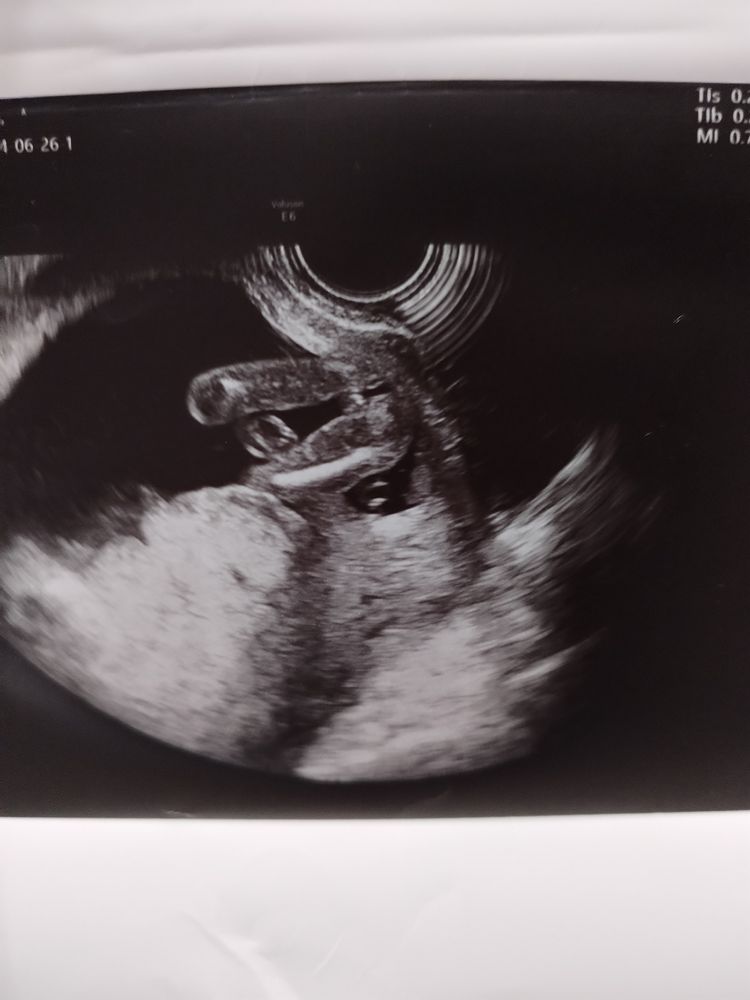

16 недель определение пола

Ну на мальчика не похоже вообще )). Но на всякий случай до 2 скрининга лучше не брать ничего. Просто наполняйте корзину)

Девочка🥰

Тут точно кофейное зёрнышко, тоисть дочка

Девочка

Так видно же кофейное зернышко😄🎀

мне кажется, тут 100% девочка!

Я всегда хожу в 16 недель и всегда говорят точно какой пол, но я делаю у хорошего врача на хорошем аппарате узи. У вас тоже все четко видно)

Пол малыша в 12,6 недель 🤔 Узнали пол в 16 недель